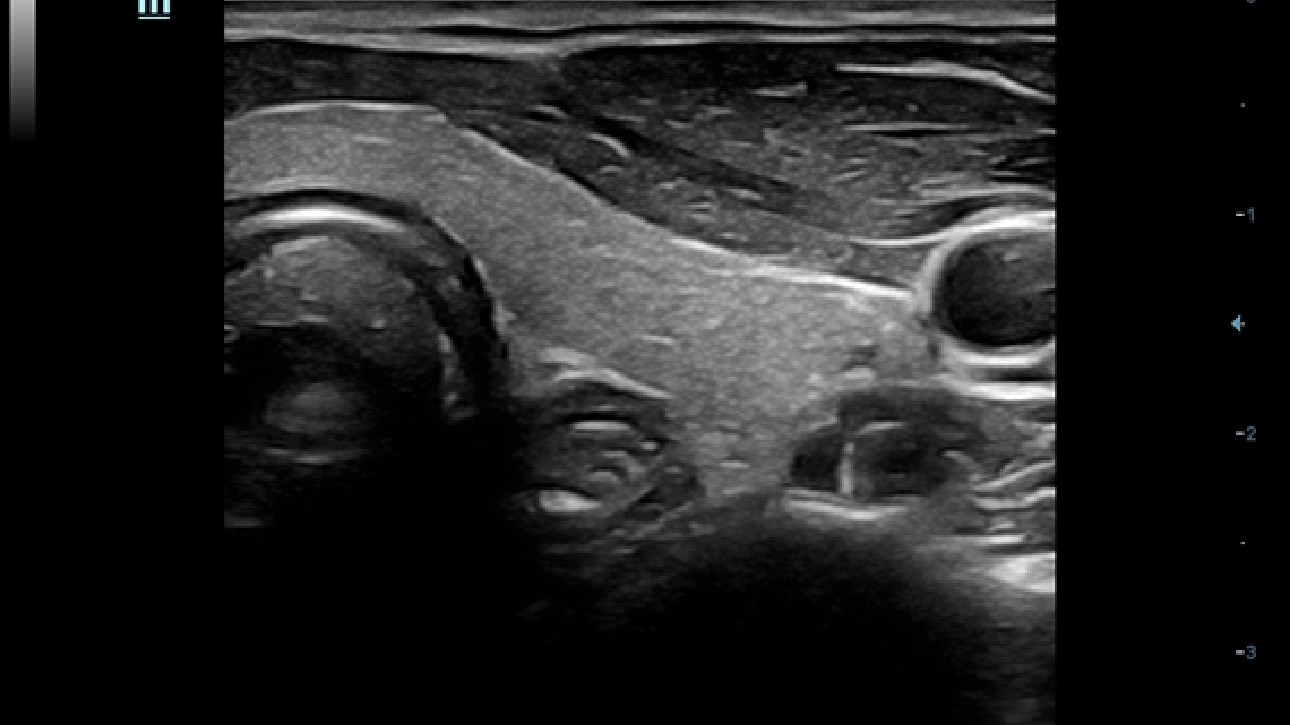

X-Insight ├© una soluzione completa studiata per offrire la migliore qualit├Ā diagnostica.

La nuova soluzione di Mindray ├© la traduzione pratica delle esigenze quotidiane dei clienti in soluzioni cliniche, il tutto con tecnologie ad ultrasuoni all'avanguardia ed in continua evoluzione.

Proponendosi come partner affidabile, DC-60 Exp con X-Insight si concentra su ci├▓ che conta veramente, semplificando la gestione della pratica clinica quotidiana con facilit├Ā e sicurezza.

Progettato per rispondere al meglio alle esigenze del cliente, DC-60 Exp con X-Insight ├© studiato per offrire un'efficienza elevata nel campo dell'imaging di precisione, grazie a una chiarezza immediata (eXpress Clarity), allŌĆÖeccezionale intelligenza (eXceptional Intelligence), oltre a vantare una lunghissima esperienza (eXceeding Experience).